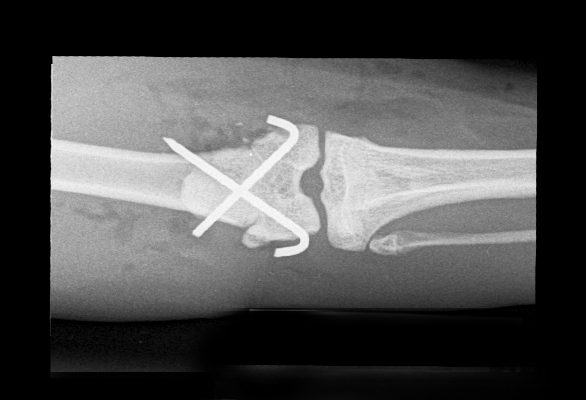

Surgery aims to realign and stabilise the fractured bones to allow uneventful healing. There are numerous methods used to stabilise the fractured bone including the use of plates, screws, pins, and wire. These are hidden from view and placed under the skin (internal fixation).

Drag the circle to view before and after surgery images.